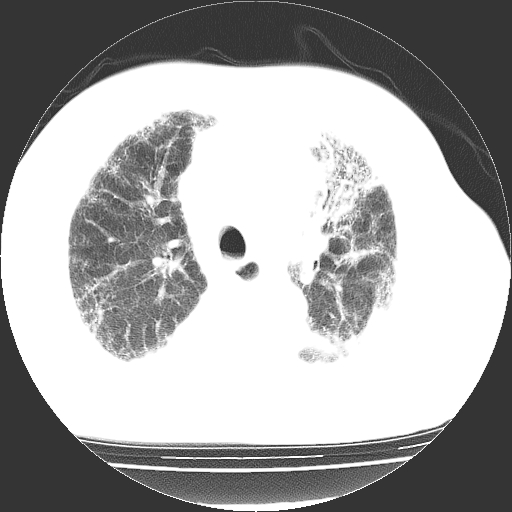

男,68岁,咳嗽、胸闷、发烧三天,查体:双肺散在湿罗音。

首先考虑特发型肺间质纤维化;两侧少量胸腔积液。

依据:1、两肺广泛条索状、网格状、蜂窝状改变。

双肺多发条索状、网格状及小灶状密度增高影。考虑慢支合并感染.间质纤维化,双侧少量胸腔积液

两肺广泛条索状、网格状、蜂窝状改变。肺间质纤维化,肺心病,双侧胸腔积液